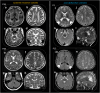

Methods: In this study, we present clinical and genetic data from 25 patients with biallelic NOTCH3 variants and conduct a literature review of another 25 cases (50 patients in total). Brain magnetic resonance imaging (MRI) were analysed by expert neuroradiologists to better understand the phenotype associated with biallelic NOTCH3 variants.

Findings: Our systematic analyses verified distinct genotype-phenotype correlations for the two types of biallelic variants in NOTCH3. Biallelic loss-of-function variants (26 patients) lead to a neurodevelopmental disorder characterised by spasticity, childhood-onset stroke, and periatrial white matter volume loss resembling periventricular leukomalacia. Conversely, patients with biallelic cysteine-involving missense variants (24 patients) fall within CADASIL spectrum phenotype with early adulthood onset stroke, dementia, and deep white matter lesions without significant volume loss. White matter lesion volume is comparable between patients with biallelic cysteine-involving missense variants and individuals with CADASIL. Notably, monoallelic carriers of loss-of-function variants are predominantly asymptomatic, with only a few cases reporting nonspecific headaches.